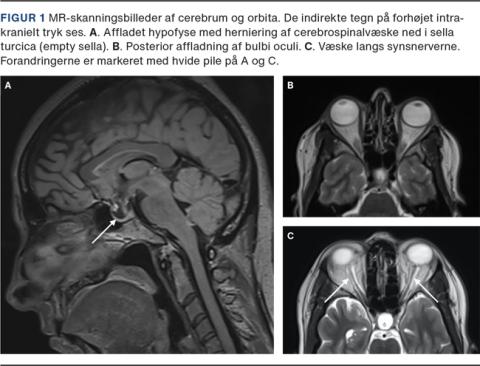

Tidlig neuroradiologisk udredning er afgørende for at udelukke strukturelle årsager til forhøjet ICP, f.eks. rumopfyldende processer eller sinusvenetrombose, samt strukturelle årsager til pulsatil tinnitus, f.eks. durale arteriovenøse fistler [3]. Forud for diagnostisk LP bør rumopfyldende processer og sinusvenetrombose udelukkes hos alle patienter. Hvis der ikke er foretaget MR-skanning af cerebrum i den akutte fase, bør den foretages subakut. MR-skanning af cerebrum kan vise indirekte tegn på forhøjet ICP: affladning af hypofysen og herniering af CSV ned i sella turcica (empty eller partiel empty sella), udvidelse af synsnerveskederne pga. CSV-ophobning omkring nn. optici, abnormt snoede nn. optici samt posterior affladning af øjet (Figur 1). Ved cerebral venografi kan der ofte ses bilateral stenose af sinus transversus. For optimal fremstilling af bulbi oculi og nn. optici kræves der specifikke orbitale MR-skanningssekvenser med fedtsuppression og tynde koronale snit. Skanningen bør beskrives af en neuroradiolog med kendskab til IIH. Ingen af ovennævnte fund er tilstrækkeligt sensitive eller specifikke til at be- eller afkræfte en IIH-diagnose, og de kan forekomme som tilfældige fund. Diagnosen af IIH er stadig klinisk, og mens tilstedeværelsen af ≥ 3 neuroradiologiske tegn på forhøjet ICP øger specificiteten markant, bør diagnosen aldrig stilles alene ud fra billeddiagnostiske fund [5, 14]. Fænotypisk præsentation kombineret med fund af både stasepapiller og forhøjet ICP er de vigtigste elementer i diagnostikken.